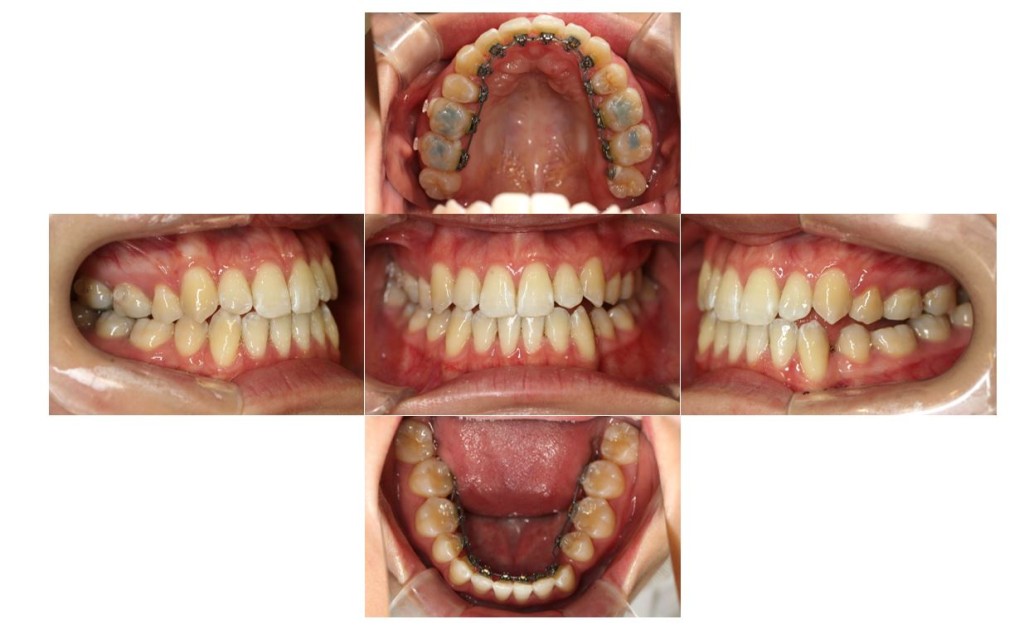

| 主訴 | 下の歯が、上の歯より前に出ていて顎が出ているのが気になる。受け口を治したい。でこぼこもあり歯磨きにしくいので、虫歯予防のためにも綺麗に並べたい。 |

| 治療期間 | 2年2ヶ月(29回) |

| 抜歯 | 有(左上4、左下5、上下親知らず4本) |

| 矯正の装置 | 裏側矯正(舌側矯正) |